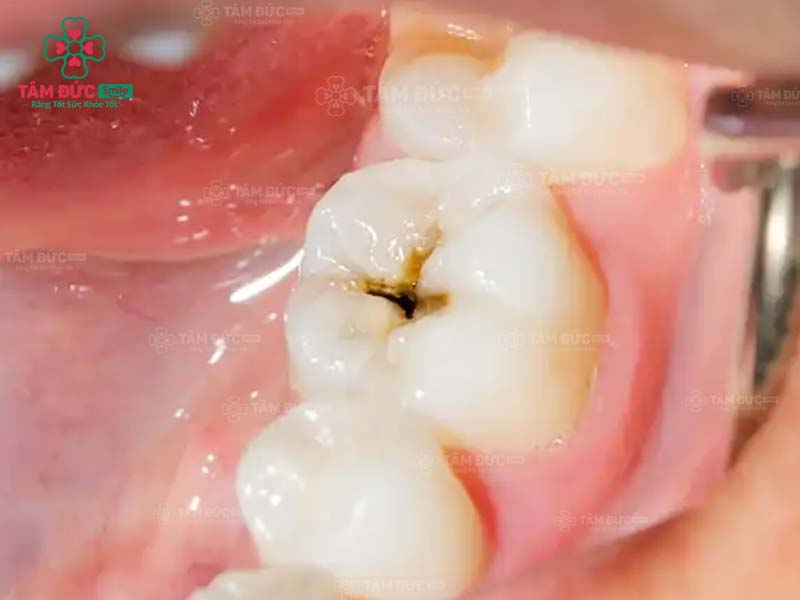

1.1. Răng bị sâu

Khi răng bị sâu, trên thân răng xuất hiện các lỗ nhỏ li ti. Đây chính là vị trí trú ngụ của hàng nghìn loại vi khuẩn. Cùng với thói quen chăm sóc răng miệng không tốt, ăn thực phẩm chứa nhiều đường, lỗ sâu răng sẽ lớn dần và gây đau nghiêm trọng. Nguy hiểm nhất chính là nhiễm trùng và mất răng vĩnh viễn.

Trám răng giúp lấp đầy các lỗ hổng trên thân răng. Nhờ đó, các triệu chứng khó chịu, biến chứng do răng sâu được loại bỏ triệt để. Thẩm mỹ của chiếc răng bị sâu nói riêng và cả hàm răng nói chung đều được phục hồi.

răng sâu cần trám răng

răng hàm bị sâu

răng nanh bị sâu cần trám